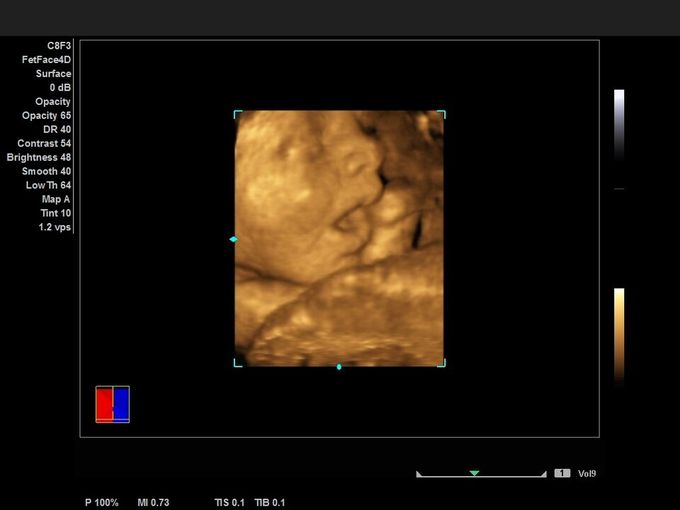

Кроме новой техники, можно заказать восстановленные медицинские системы: ультразвуковые сканеры, томографы, флюороскопы, ангиографы и хирургические установки С-дуга.